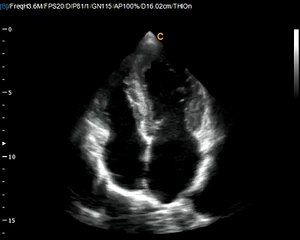

Chison Q9 Cardiac PW Pulse wave Anazing quality for a low cost color doppler ultrasound machine